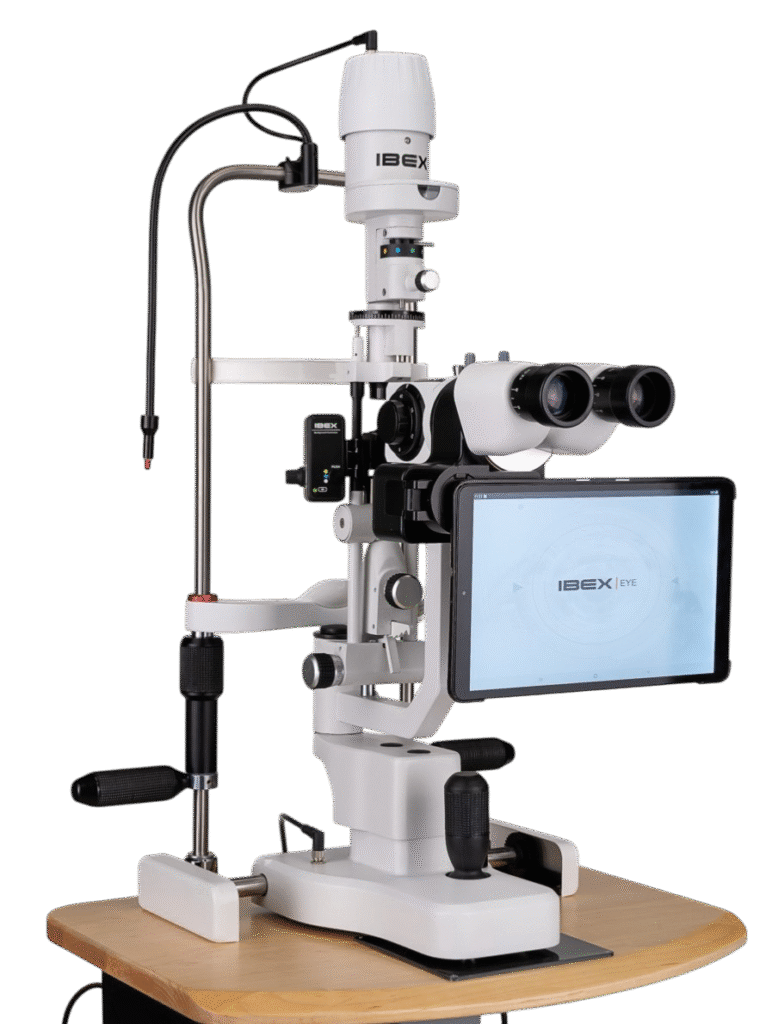

Opteon™ Slit Lamp Imaging + Meibography

Photos & Videos. Clinical Documentation. Patient Education. Reimbursement.

Illuminate your exams and transform patient engagement like never before. When patients see detailed images of their eyes, they gain a deeper understanding of their health and recognize the importance of compliance and follow-up care. Throughout development, our team saw firsthand the profound impact of imaging in the clinic—watching patients smile, express genuine appreciation, and embrace their health journey. That unforgettable experience remains the most rewarding part of our work.

Opteon was born and developed in the clinic, meticulously tested, and perfected through countless hours to ensure that it flows with your exam routine — delivering unmatched reliability and efficiency.

Pushing ahead, our imaging system includes our new, patent-pending Halo background light. Working with native slit lamp illumination, Halo delivers unparalleled clarity of the ocular adnexa. You’ll uncover details of the meibomian glands, acinar spaces, conjunctiva, lid margins, and lashes like never before.